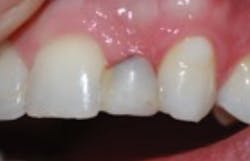

After a three-month integration period, final impressions were taken for a screw-retained crown. The procedure was noneventful, and not only was the patient happy having a provisional tooth, but the relief offered with a permanent fixed solution changed his entire outlook (figures 5 and 6).

Figure 2: Failing Maryland bridge

Figure 6: Final implant restoration